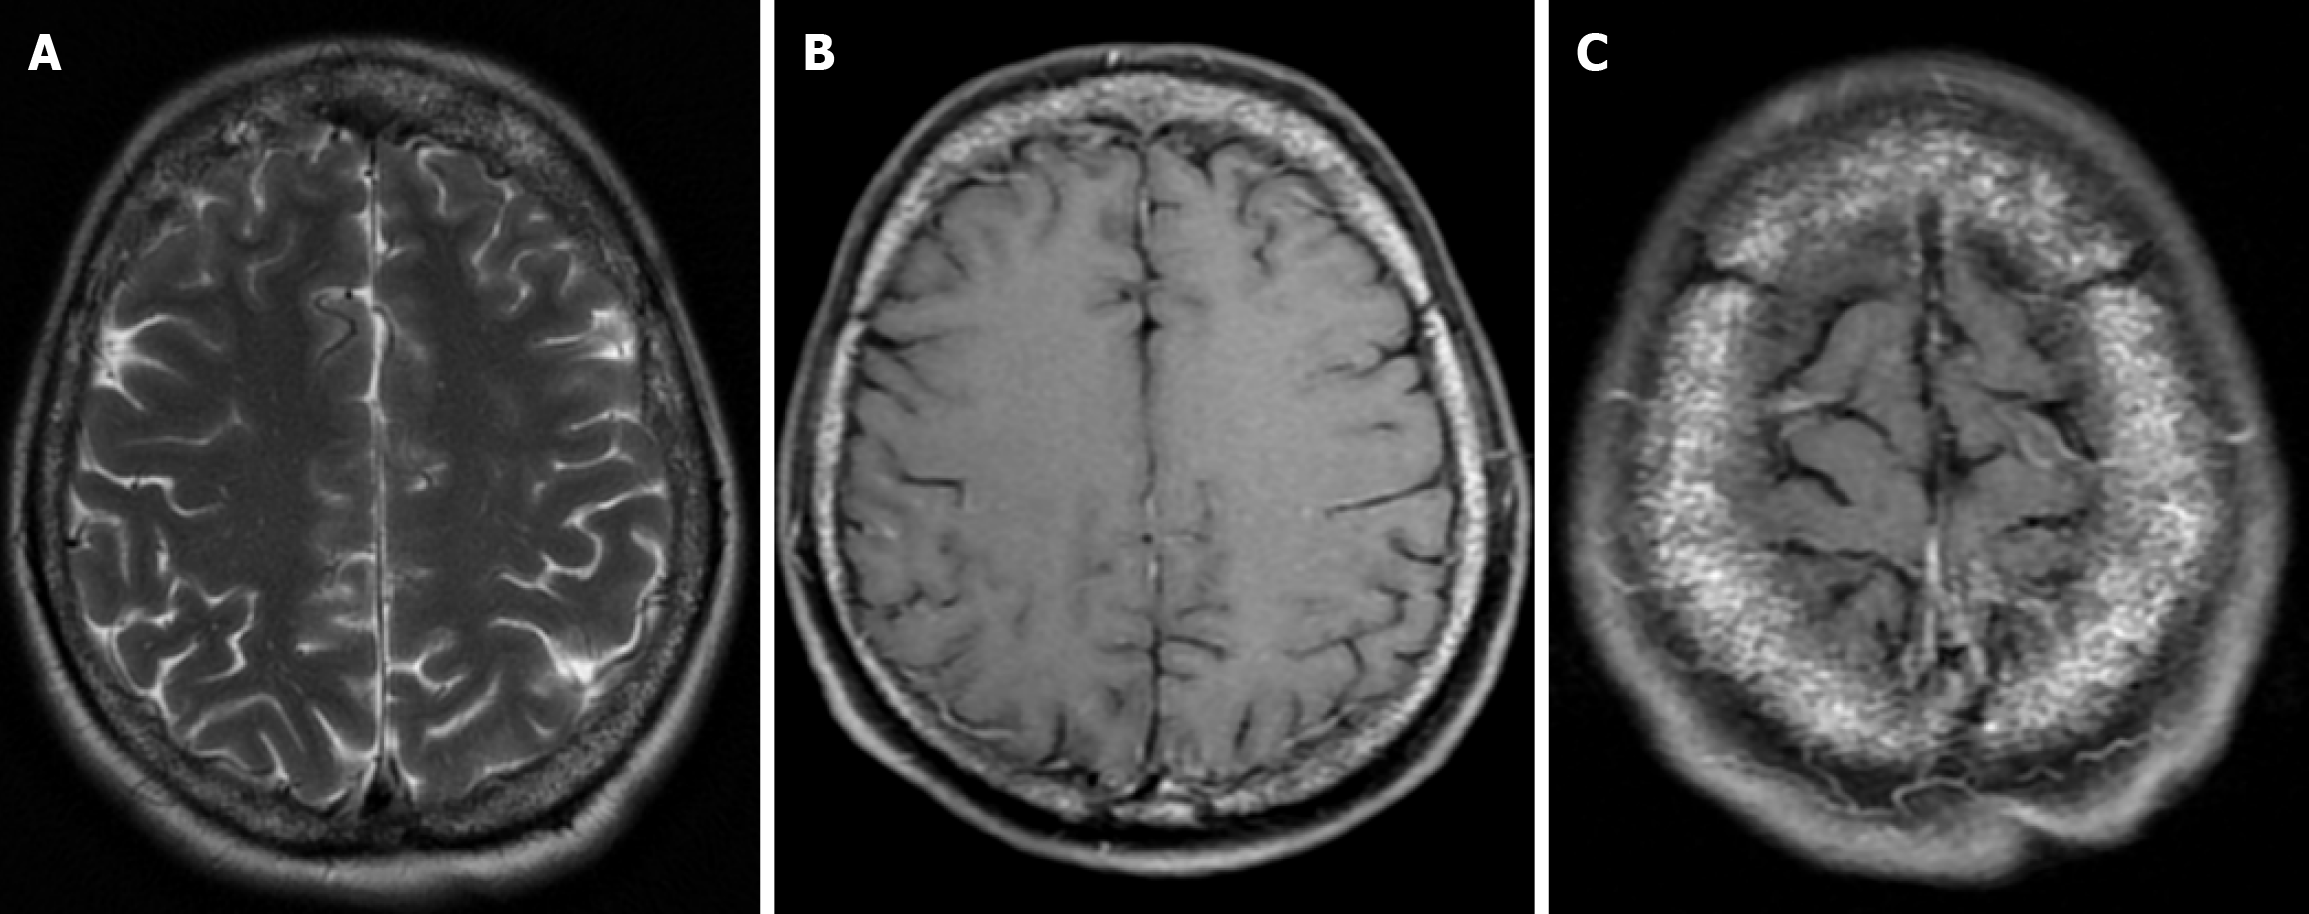

Epidermoid cysts are small or medium-sized, benign, and slow-growing tumors that arise from the remnants of ectodermal cells in the bones of the skull. These cysts can also develop after trauma or surgery. Epidermoid cysts are lined with squamous epithelium. They contain deposits of cholesterol and keratin. These cysts constitute less than 1% of primary intracranial tumours, while intradiploic epidermoid cysts account for less than 0.25% of intracranial tumours. These tumors can occur at any age from the first decade of life to the seventh decade, with a mean age of 32-38 years, and there is no gender predilection. Epidermoid cysts are most commonly found in the frontal, parietal and occipital regions and often involve more than one bone. Epidermoid cysts appear on plain radiography as round or lobulated lytic areas with smooth and sclerotic margins. On CT they appear as non-contrast enhanced intradiploic lytic hypodense lesions with smooth sclerotic borders. Epidermoid cysts often cause remodeling and widening of the inner and outer tables. Epidermoid cysts that appear hyperdense on CT due to bleeding, calcification or high protein content are called white epidermoids and are observed quite rarely. On MRI, epidermoid cysts appear isointense/hyperintense on T2-weighted and fluid-attenuated inversion recovery (FLAIR) images and slightly hyperintense on T1-weighted images (Figure 4). These lesions restrict diffusion on diffusion-weighted imaging but show no contrast enhancement on contrast enhanced sequences[19].

The beaten copper skull shows prominent convolutional markings on several bones of the skull. These convolutional markings normally appear between the ages of 2-3 and 5-7 years, which are periods of rapid brain growth. The occurrence of convolutional markings in children younger than 18 months should suggest a cause leading to increased intracranial pressure due to processes such as obstructive hydrocephalus, craniosynostosis or intracranial masses. Beaten copper skull pattern develops because of pressure applied to the soft skull by the growing brain. The beaten copper skull is usually confined to the posterior part of the inner table of the skull, but this appearance can affect the entire skull. Plain radiography of the skull can be an important diagnostic tool to detect increased intracranial pressure. In children, CT and three-dimensional reconstructions are best used to evaluate the convolutional markings (Figure 5) and cerebral ridges for surgical planning[23].